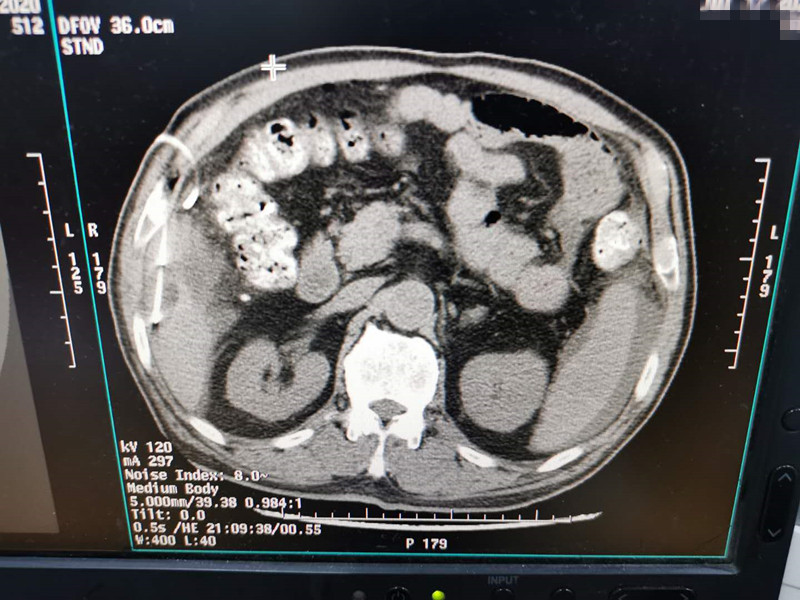

83岁肺部氩氦刀冷冻消融